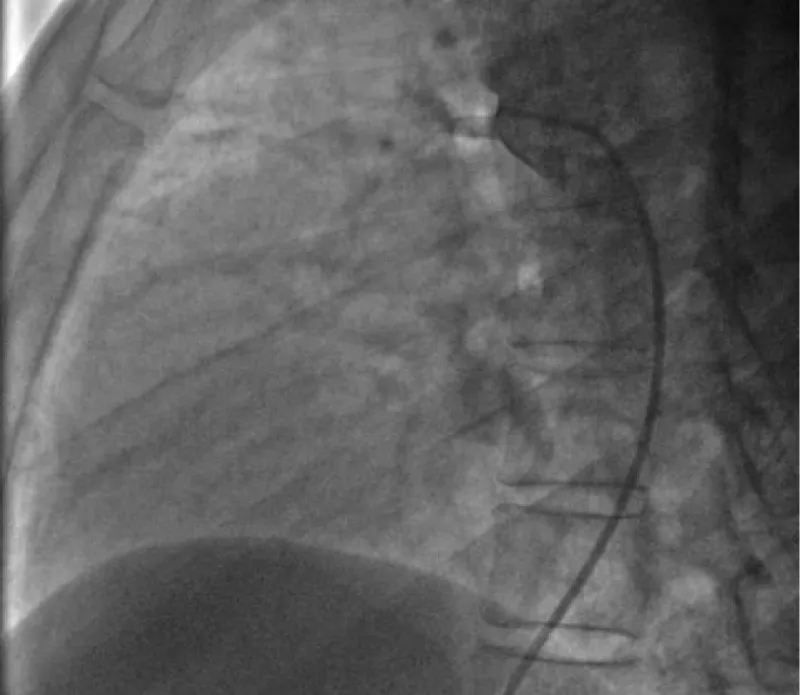

(A) PostPDA closure TTE LVEDD of 5.1 cm. (B) Followup TTE closure of Pda Closure Recovery Time the nonsurgical, minimally invasive pda closure procedure is performed by an interventional cardiologist with significant. transcatheter closure of patent ductus arteriosus (pda) in premature infants is a feasible, safe, and an effective alternative to surgical ligation and may be. the cardiologist will check from time to time to see if the pda is closing on its own.. Pda Closure Recovery Time.